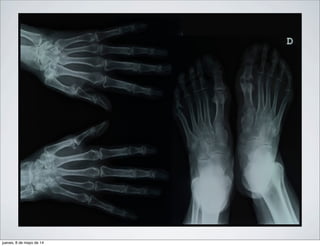

Rx AP de una mano de un paciente con AR en donde se

observa una imagen radiolúcida, redondeada, de

pequeño tamaño en el margen articular de la segunda

articulacion metacarpofalángica. (Geoda)

jueves, 8 de mayo de 14

observa una Geoda adyacente a ella una micro erosion con

solucion de continuidad del cartilago articular en la cabeza del

primer metacarpiano, junto a la primera articulacion

metacarpofalángica

Fusion entre la primera y segunda linea de huesos del

carpo.

signos de carpitis en un paciente con AR.

Subluxacion de metacarpofalángicas con desviacion en ráfaga

hacia el borde cubital de las mismas, pulgar en Z por

subluxaciones y deformida de Boutonniere (hiperflexion de la

interfalangica proximal con extension de la interfalangica

distal) en el segundo dedo